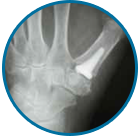

PROTESI POLSO E MANO

CHIRURGIA DELLA MANO: lesioni tendinee e nervose, S.T.C., M. di Dupuytren, rizoartosi, protesi in pirocarbonio dita, carpo e polso.